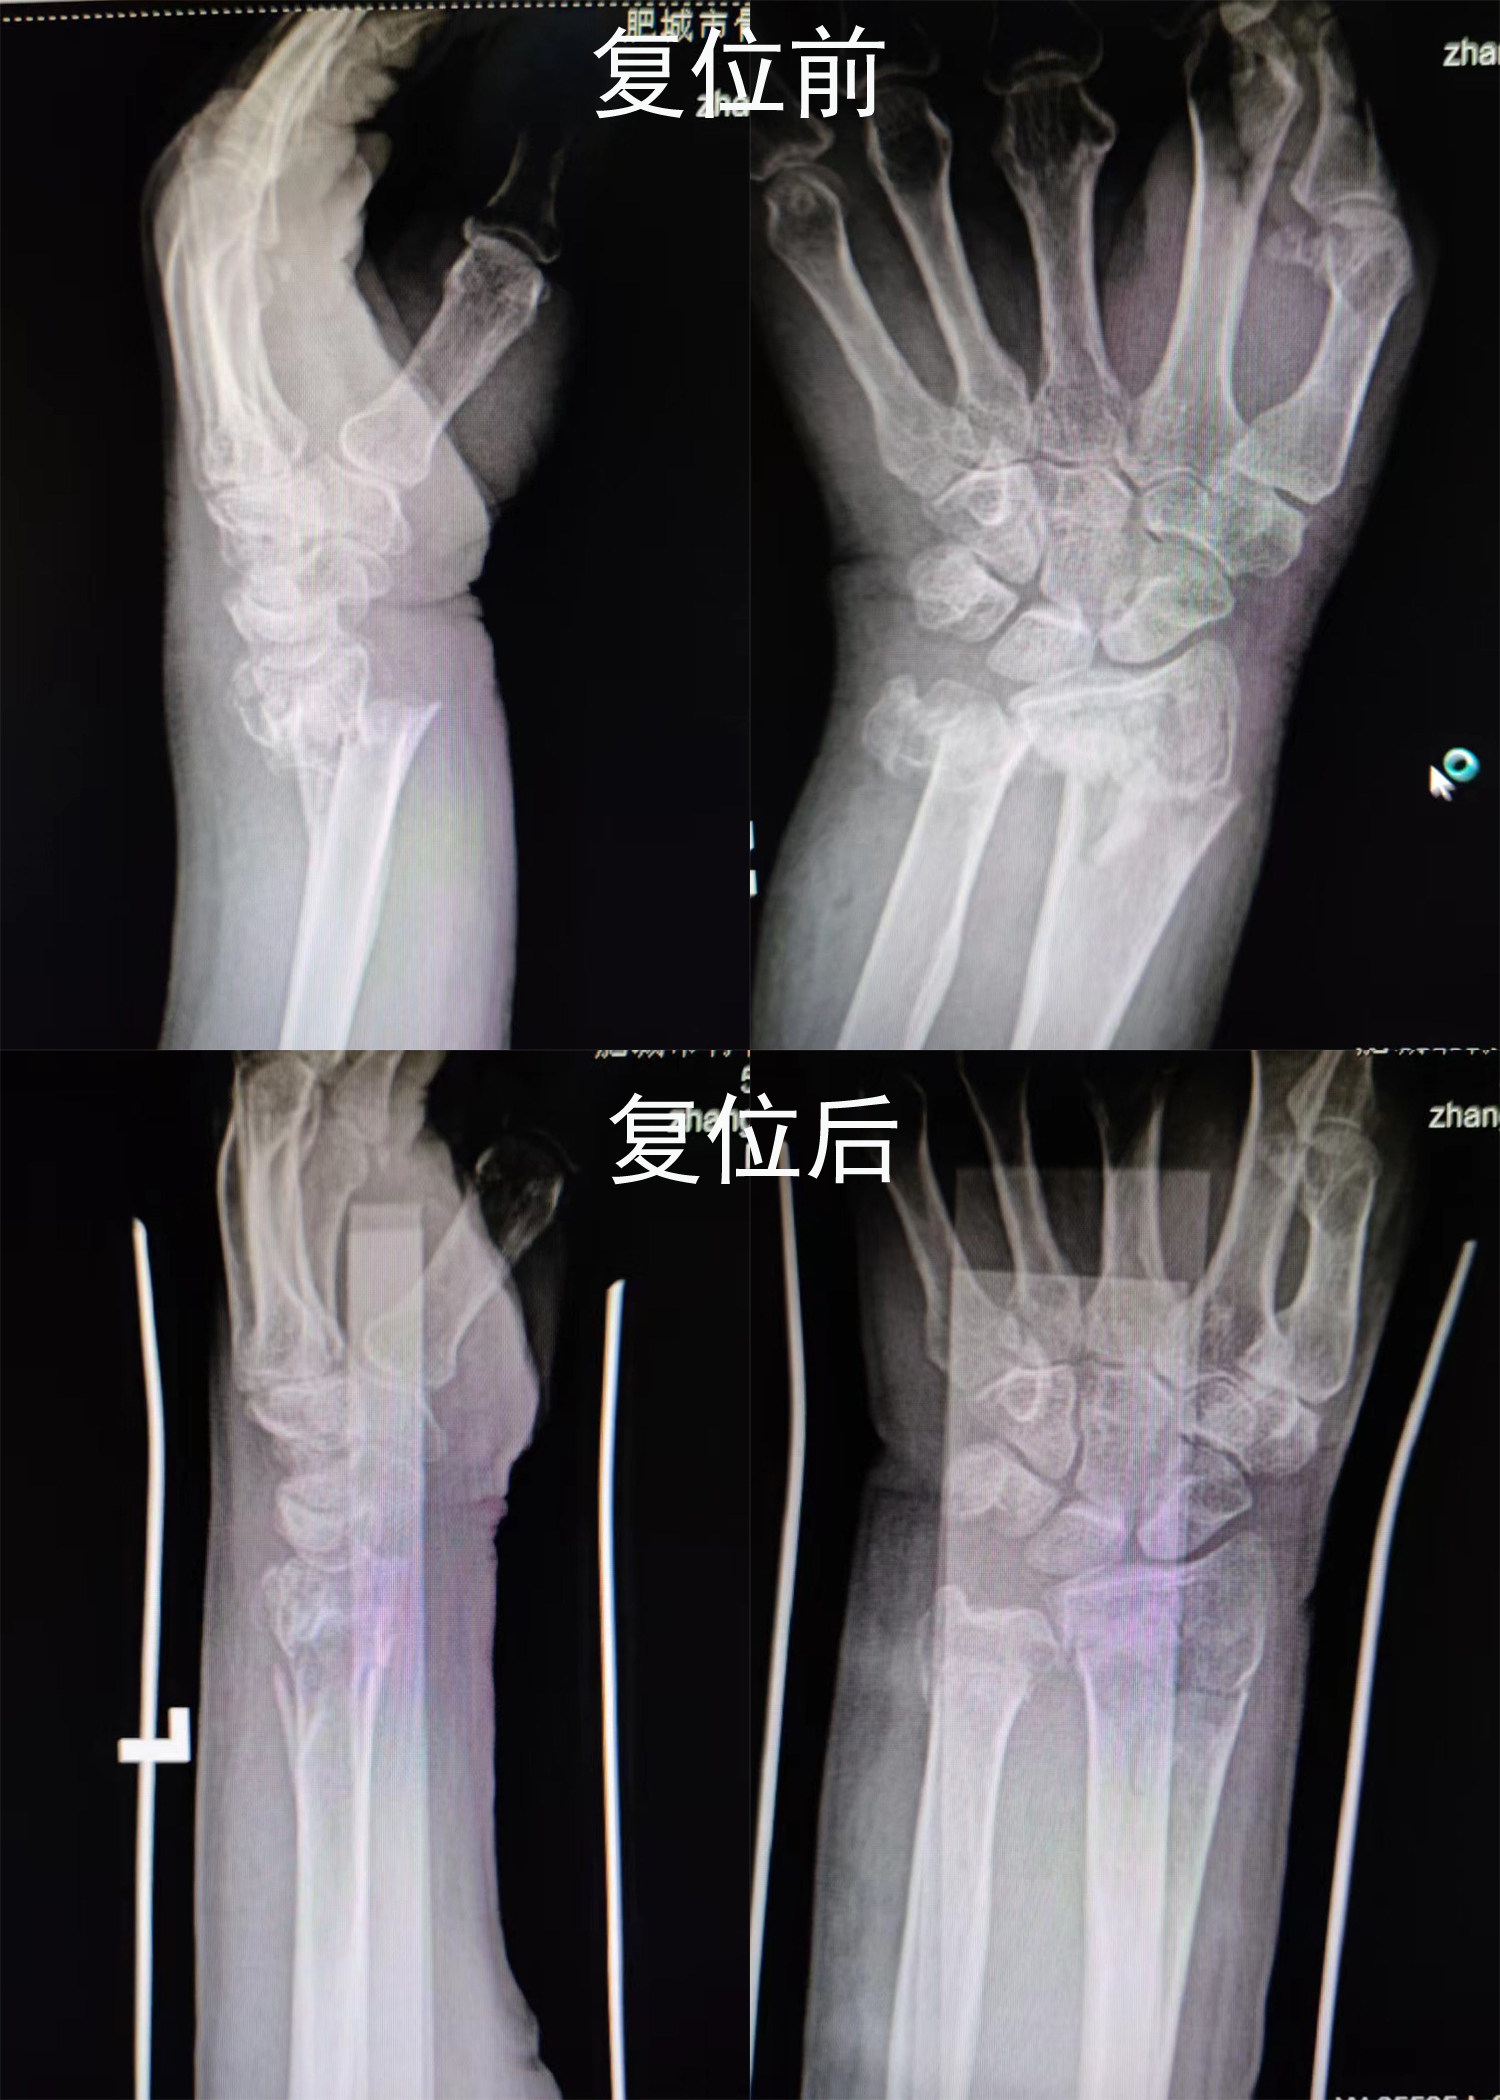

梁氏正骨-梁光兴正骨案例